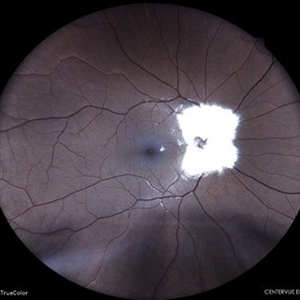

STATUS POST PAN-RETINAL PHOTOCOAGULATION

Oct 11 2022 by Akansha Sharma

COLOUR FUNDUS PHOTO OF A 71 YEAR OLD MALE WITH SCARRING POST PAN-RETINAL PHOTOCOAGULATION

Photographer: Dr. Akansha Sharma-Retina Foundation, Ahmedabad

Condition/keywords: laser photocoagulation, pan-retinal photocoagulation (PRP)